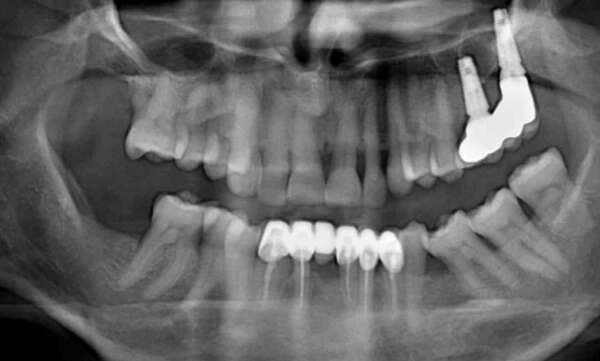

Un bridge est une prothèse fixe permettant de remplacer une ou plusieurs dents manquantes en s’appuyant sur les dents adjacentes. Les dents sur lesquelles s'effectue l'appui doivent être préparées pour accueillir le bridge.

Il existe plusieurs techniques de remplacement d’une ou plusieurs dents, dont le bridge qui s’intègre naturellement au reste de la dentition et permet une restauration esthétique et fonctionnelle. Selon le contexte clinique, différents types de bridges pourront être proposés.